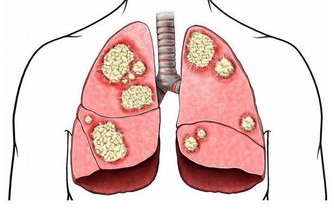

2.吃完雞蛋後不要立即吃柿子

吃完雞蛋後吃柿子輕則會得食物中毒,總則會導致急性腸胃炎還有肺結石。一般而言,這兩種食物同時吃會導致以上吐、下瀉、腹痛為主的急性胃腸炎癥狀。所以如果服用時間在1~2小時內,可使用催吐的方法。立即取食鹽20g加開水200ml溶化,冷卻後一次喝下,如果不吐,可多喝幾次,迅速促進嘔吐。或者可用鮮生薑搗碎取汁用溫水沖服。如果服用時間較長,儘快服用些瀉藥將有毒物質排除體內。